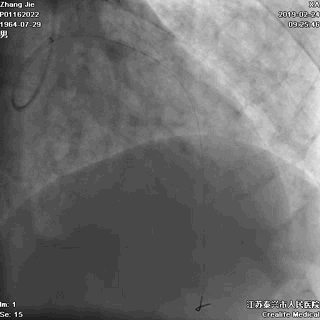

四、IABP植入

左冠恢复血流后,患者的血压仍然偏低,我们决定植入IABP。

经左侧股动脉途径植入IABP

用了不到十分钟,我们就完成了主动脉气囊反搏导管的植入。IABP植入后,患者的血压就比较容易控制到接近正常的水平。